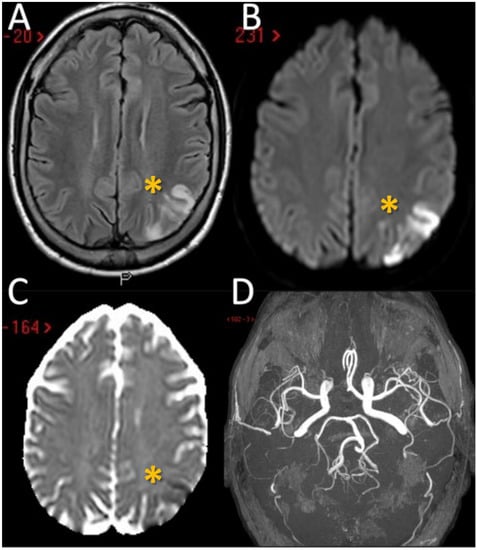

The third patient is a 69-year-old woman with a remote history of herpetic encephalitis and transient global amnesia who arrived at the Emergency Room after developing low grade fever and bilateral visual blurring. Multiple synchronous ischemic lesions, located bilaterally, both in infra- and supra-tentorial regions, mainly in border zones, with a prevalent involvement of the occipital lobes were evident on neuroimaging without large vessel occlusion or stenosis were found (Figure 3A–E).

Another relevant issue is that external and internal border zone infarcts may have a different pathogenesis, which may be inferred by neuroimaging appearance. As shown in Figure 5 (green triangles), external border zone infarcts usually are wedge-shaped and their hemodynamic origin is hard to define only on the neuroimaging basis because of the wide variability of arterial territories and leptomeningeal collaterals. Therefore, isolated external border zone infarctions may be embolic rather than purely hemodynamic and they may be associated to small cortical infarcts. The cause of unilateral posterior external border zone infarcts is more often embolic than hemodynamic; on the contrary, bilateral infarcts are more likely to be caused by underlying hemodynamic impairment [21]. Instead, internal border zone infarcts are usually multiple and occur in a rosary-like pattern (as seen in Figure 2 for the second patient we described). A unique widely shared definition of this pattern does not exist; it has been assumed from one of the first reports that the rosary-like pattern is a series of three or more lesions, each with a diameter of 3 mm or more, arranged in a linear pattern parallel to the lateral ventricle in the centrum semiovale or corona radiata [22]. Internal border zone infarcts are also categorized as partial or confluent [12]; partial infarcts are large, elongated (cigar shaped), and arranged in a line parallel and adjacent to the lateral ventricle, looking like the beads of a rosary. It has been postulated that the duration of hemodynamic impairment is related to a partial o confluent appearance, respectively with a shorter and longer lasting impairment [23]. The main neuroimaging differential diagnosis of internal border zone infarcts is represented by superficial perforator (medullary) infarcts, caused by caused by the occlusion of medullary arteries arising from pial plexuses, because of the similar appearance on MRI. Usually they are smaller, more superficially located and widely scattered than internal border zone infarcts and they have a tendence to spare the paraventricular regions, more typically affected in internal border zone infarcts. The hemodynamic factor is much more evident in internal border zone infarcts than in external border zone infarcts, mainly because the greater vulnerability of the internal border zone due to anatomical feature of the supplying arterioles. Indeed, internal border zones are supplied by medullary penetrating vessels branching from MCA and ACA and by deep perforating lenticulostriate branches. The first ones are the most distal internal carotid artery (ICA) branches with the lowest perfusion pressure. The second ones have poor collateral supply, and unfortunately, there are no anastomoses between the deep perforators and the white matter medullary arterioles [16]. The consequence of this anatomical organization of the cerebral vasculature is that the centrum semiovale and corona radiata are more susceptible than other brain regions to hemodynamic-related ischemia. Conversely, the external border zone is closer to the cortical surface, where shorter penetrating arteries originate, and it has a better chance of developing a collateral supply through leptomeningeal or dural anastomoses [13,16]. The higher probability of hemodynamic impairment may be predicted when external and internal border zone infarctions co-occur. Although more known in the supratentorial compartments, there is a corresponding border zones organization in the cerebellum. Border zone infarcts in the cerebellum are usually less than 2 cm in size and are located at the borders of the anterior inferior cerebellar artery (AICA), superior cerebellar artery (SCA), posterior inferior cerebellar artery (PICA), and their branches. The pathophysiology of cerebellar border zones infarctions is similar to the one of supratentorial border zone infarctions, combining the hemodynamic and embolic hypotheses. As expected, small border zone lesions may coexist with large territorial infarctions. The bilateral cerebellar infarcts shown in Figure 3 for the third patient may have a predominantly hemodynamic (border zone between lateral and medial branches of PICA o both sides) than embolic pattern, whereas supratentorial infarctions in the same patient have a clear territorial pattern.

Figure 3. Neuroimaging studies of the third patient. MRI of patient 3 showed the presence of multiple supratentorial (A) and infratentorial (B) hyperintense lesions (yellow asterisk) with a territorial distribution in A and border zone pattern in B (axial FLAIR sequences) with DWI and ADC pattern suggesting acute ischemic lesions with a metachronous timing pattern (C,D). In the follow-up CT performed 7 days later it is evident the increased number of ischemic lesions, in particular on the right hemisphere (E).